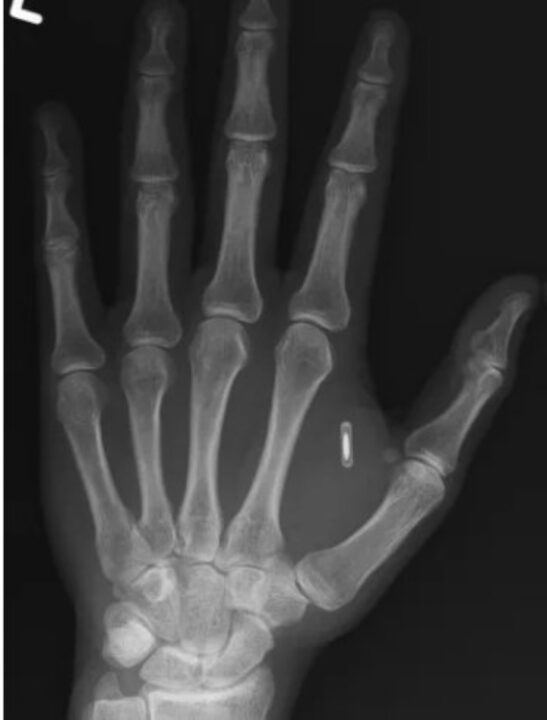

O mágico Zi Teng Wang, que atua sob o nome artístico Zi the Mentalist, partilhou recentemente a sua história, através do Facebook, mostrando uma imagem de raio-X com um objeto entre o polegar e o indicador da mão.

Segundo ele, citado pelo TechSpot, a imagem mostra a sua mão e um microchip RFID, que ele próprio implantou ali há vários anos.

Imagem partilhada pelo mágico Zi Teng Wang, que atua sob o nome artístico Zi the Mentalist. O raio-X mostra um chip RFID entre o polegar e o indicador da mão.